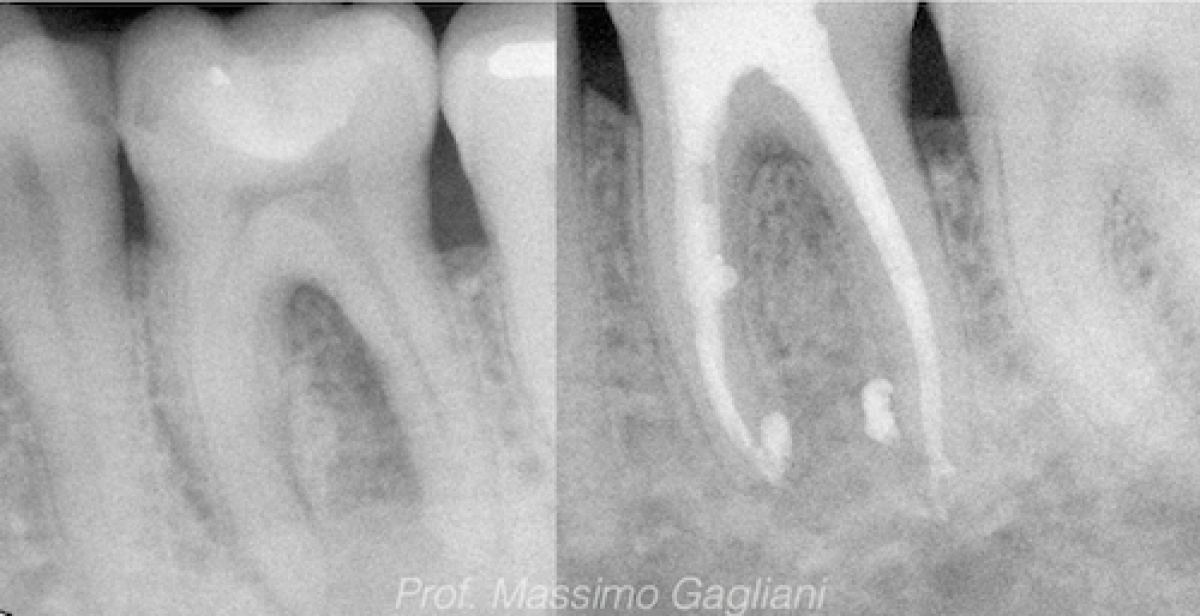

preoperative periapical and clinical image. primary endodontic lesion Endodontic Lesion Origin The goal of endodontic treatment is to clean, shape, and seal the root canal system. However, the sulcular sinus tract has been patent for sufficient time for biofilm and calculus to form on the root surface. However, the prognosis of the condition varies from good. Lesions of endodontic periodontal origin. As the name implies, the etiology of a primary endodontic. Endodontic Lesion Origin.